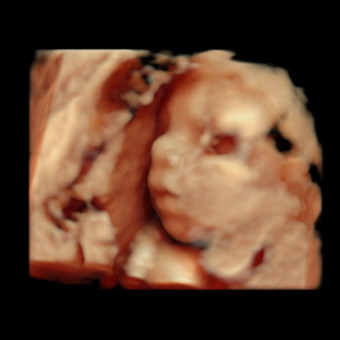

Baby Duffy #2

Olivia & Zac Duffy

Kearneysville, WV

April 2026